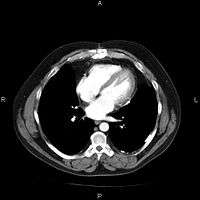

A picture archiving and communication system (PACS) is a medical imaging technology which provides economical storage and convenient access to images from multiple modalities (source machine types).[1] Electronic images and reports are transmitted digitally via PACS; this eliminates the need to manually file, retrieve, or transport film jackets. The universal format for PACS image storage and transfer is DICOM (Digital Imaging and Communications in Medicine). Non-image data, such as scanned documents, may be incorporated using consumer industry standard formats like PDF (Portable Document Format), once encapsulated in DICOM. A PACS consists of four major components: The imaging modalities such as X-ray plain film (PF), computed tomography (CT) and magnetic resonance imaging (MRI), a secured network for the transmission of patient information, workstations for interpreting and reviewing images, and archives for the storage and retrieval of images and reports. Combined with available and emerging web technology, PACS has the ability to deliver timely and efficient access to images, interpretations, and related data. PACS breaks down the physical and time barriers associated with traditional film-based image retrieval, distribution, and display.

Most PACSs handle images from various medical imaging instruments, including ultrasound (US), magnetic resonance (MR), Nuclear Medicine imaging, positron emission tomography (PET), computed tomography (CT), endoscopy (ES), mammograms (MG), digital radiography (DR), computed radiography (CR), Histopathology, ophthalmology, etc. Additional types of image formats are always being added. Clinical areas beyond radiology; cardiology, oncology, gastroenterology, and even the laboratory are creating medical images that can be incorporated into PACS. (see DICOM Application areas).